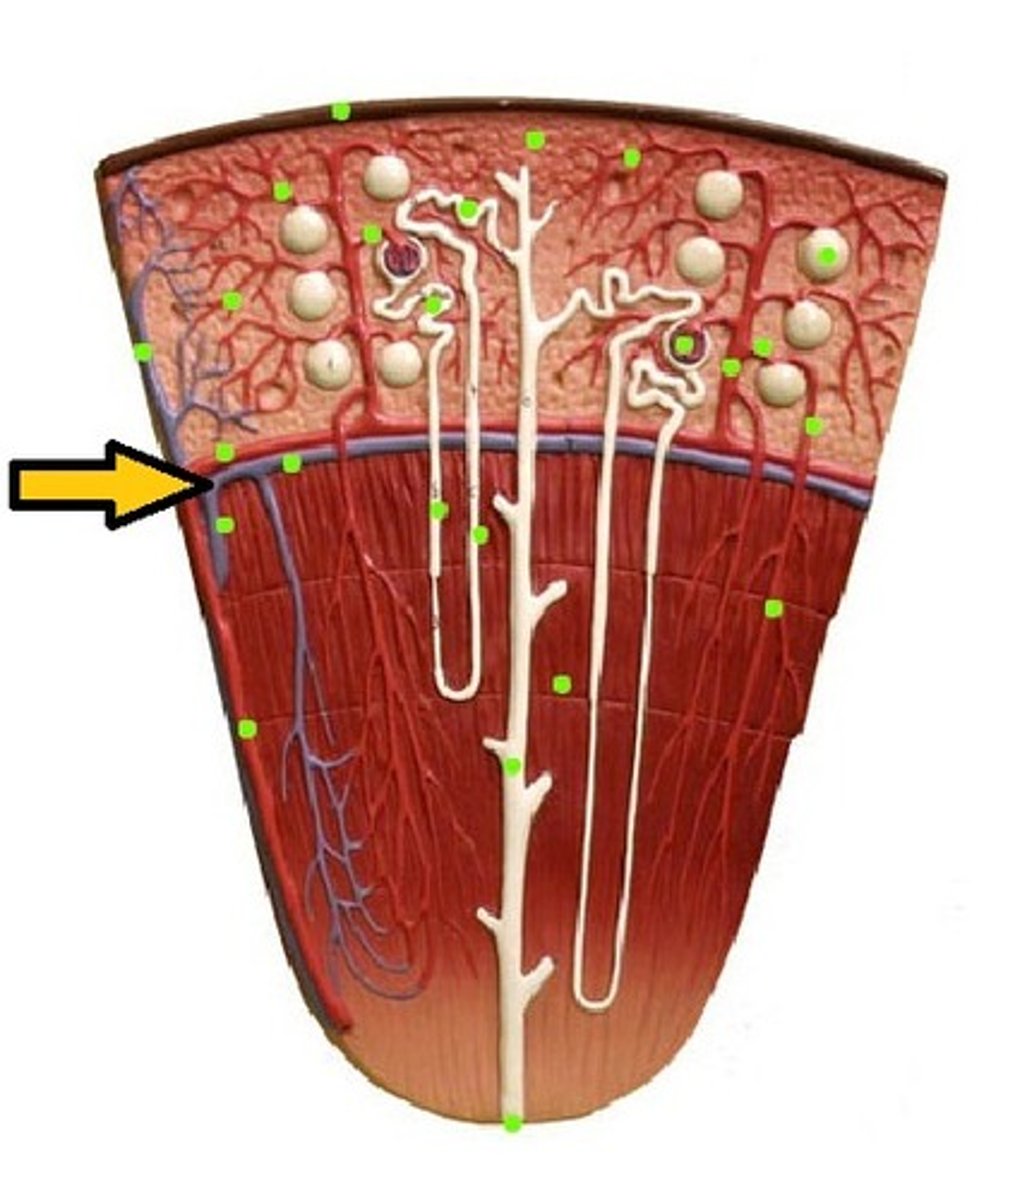

renal cortex

renal medulla

afferent arteriole

efferent arteriole

glomerulus

juxtaglomerular apparatus

Bowman's capsule / glomerular capsule

macula densa cells

juxtaglomerular cells

podocytes

capsular space

renal corpuscle

proximal convoluted tubule

descending loop of henle

ascending loop of henle

distal convoluted tubule

papillary duct

collecting duct